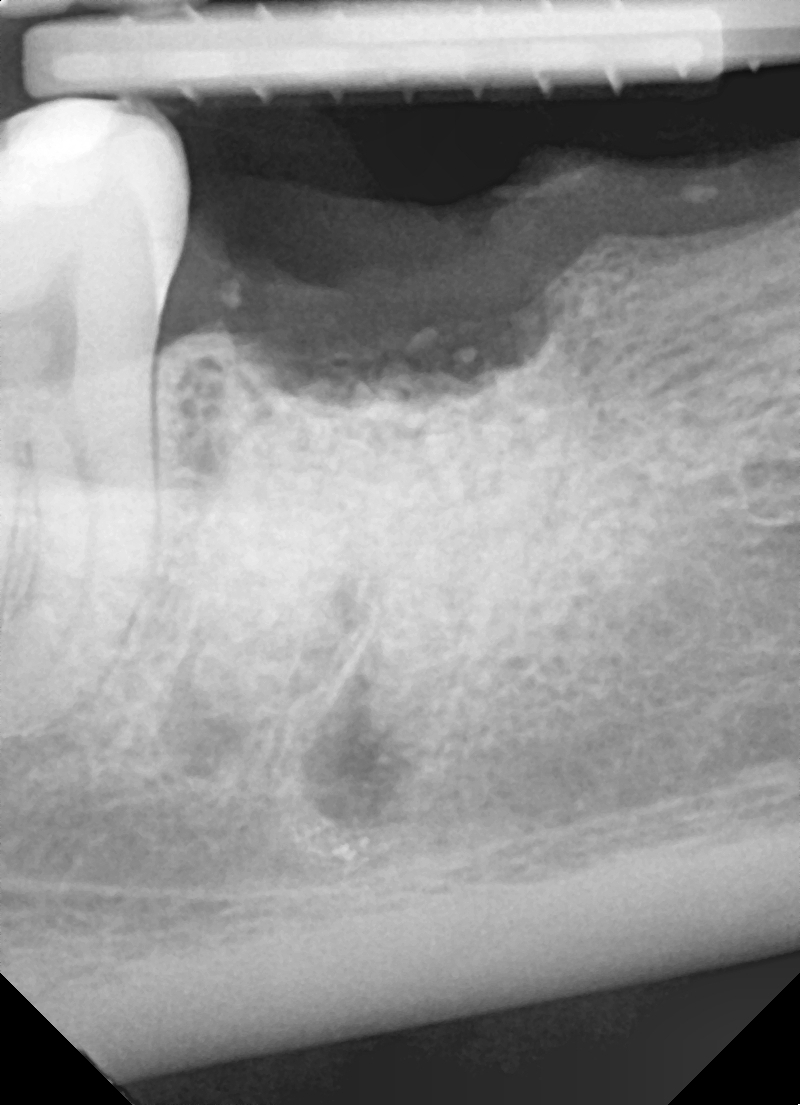

Ryc. 1a. Zmiany zapalne furkacji zęba 47.  Ryc. 1b. Rtg 7 dni po augmentacji.

Ryc. 5. RTg 7 dni po usunięciu 47 i augmentacji zębodołu